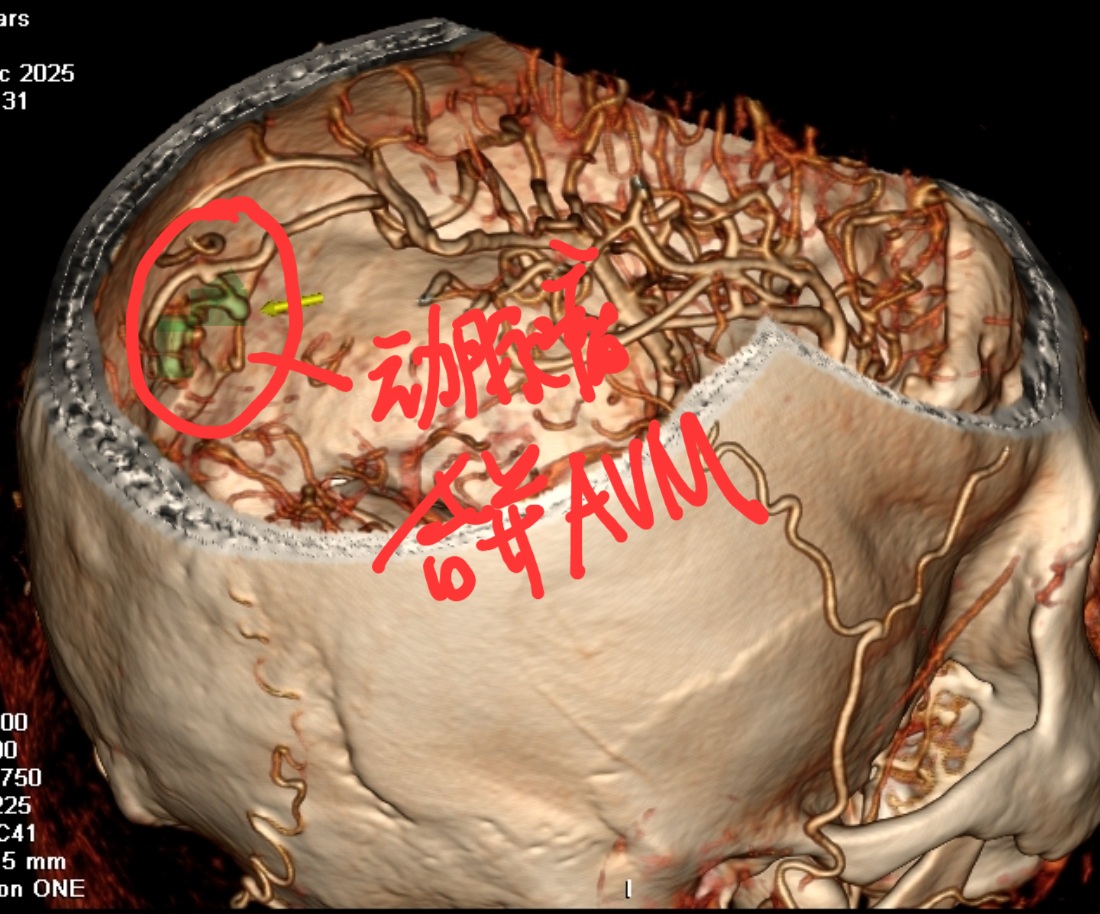

头部CTA提示:左颞顶AVM合并大脑中远端动脉瘤

手术精要:1 左颞顶大骨瓣,充分减压;2 超声定位血肿,先清除液化部分血肿;3 吲哚菁绿造影显示AVM合并动脉瘤;4 夹闭动脉瘤切除AVM;5复查吲哚菁绿造影提示AVM切除,动脉瘤夹闭毗邻血管通畅

CTA显示:AVM已切除,动脉瘤夹闭良好